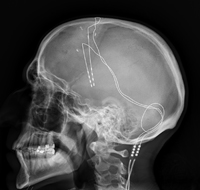

Deep brain stimulation for Parkinson’s disease

UNESCO has just introduced the first global ethical standards for neurotechnology. This rapidly advancing field receives far less public attention than AI, despite surging investment. Neurotechnology includes tools that directly interact with the nervous system to measure or influence or be influenced by brain activity. While these technologies offer major medical benefits, such as deep-brain stimulation for depression and Parkinson’s disease, or brain-computer interfaces that help people with disabilities communicate or control prosthetics, their non-medical uses remain largely unregulated. Many widely used consumer devices, including headbands and headphones, now collect neural data to track stress, sleep, or heart rate, often without users realising it. Such data can expose intimate information about thoughts and emotions and could be shared with third parties. UNESCO’s new guidelines urge governments to safeguard privacy, ensure that neurotechnology remains accessible and inclusive, and protect vulnerable groups, especially children and adolescents, whose developing brains make them particularly susceptible to harm. The standards advise against non-therapeutic use in minors, warn about workplace monitoring that could profile employees, and emphasise that explicit consent and transparency are essential. They also call for stronger regulation of products that can shape behaviour or foster addiction, requiring clear, easy to understand information for consumers.